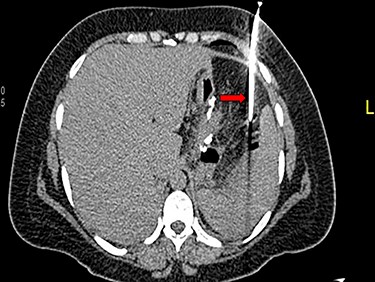

A 36-year-old obese female patient underwent a sleeve gastrectomy abroad. Eleven days after surgery, she presented with an abdominal pain. Abdominal computer tomography (CT) revealed several fluid-air collections (3 abscesses) around the upper greater gastric curve (3.5 × 3.2 cm), lesser sac (7 × 3.3 cm) as well as anterior to the spleen (7 × 3.3 cm). By that time, there was also left pleural effusion and atelectasis of the left lower lung lobe. On the next day, CT-guided aspiration was done (Fig. 1) and a pigtail catheter was inserted to drain the abscesses. On the following day, water-soluble oral contrast displayed an active contrast leak along the proximal sleeve gastrectomy (Fig. 2). On the same day, covered esophageal stent was placed endoscopically. The patient was discharged home and was scheduled for stent removal after 2 weeks. However, after 2 days, the patient presented again with an abdominal pain. The plain x-ray showed slippage of the stent distally. Upper GI endoscopy was done, and the esophageal stent was removed. One day later, the patient condition deteriorated with a massive upper GI bleeding. A CT angiography showed no extravasation and the source of bleeding was not identified during endoscopy due to massive bleeding. An immediately performed angiogram revealed an AEF (Fig. 3). The interventional radiologist achieved transient cessation of the bleeding through embolization of the fistula with interlock coils (Fig. 3). An aortogram showed continuous extravasation of contrast through the fistula, and therefore, endovascular intervention was performed with implantation of 22 mm × 112 mm aortic stent (TEVAR using Valiant covered stent - Medtronic company, USA). One week after TEVAR, another long esophageal stent was positioned (from lower esophagus to the stomach). Two weeks later, a barium swallow proved no evidence of contrast leak. Then, the esophageal stent was removed, and the patient was discharged home. There was a plan for definitive reconstruction procedure, including removal of the endovascular stent and use of reconstructed pericardial bovine graft, however, the patient declined. About 10 months later, she presented with another attack of massive hematemesis, with a drop of hemoglobin to 8 g/dl and a blood pressure of 66/44 mmHg requiring a rapid sequence induction and infusion of packed red blood cells. An immediate abdominal CT showed evidence of peri-stent infection with no contrast extravasation. Upper GI endoscopy showed an evidence of an ischemic ulcer above the Z-line with granulation tissue at the ulcer edge and erosion of the endovascular stent into the lower esophagus. The patient had a positron emission tomography (PET) scan and diagnosed with mediastinitis due to aortic stent infection and septic shock (Fig. 4). Surgical intervention was offered but the patient declined. Treatment with broad spectrum antibiotics and blood transfusion were administrated as required. Around 5 weeks later, the patient developed massive upper GI bleeding requiring intubation and surgical intervention (distal esophagectomy with removal of the endovascular stent and resection and replacement of the AEF site with reconstructed tube using 14 × 9 cm bovine pericardial graft through left thoraco-abdominal incision utilizing left cardiopulmonary bypass and distal perfusion through left femoral artery (Fig. 5). Closure of the stomach with gastrostomy tube insertion for feeding had been performed. One and half year later, reconstruction surgery of the esophagus with colonic interposition was done. After 3-year follow-up, the patient was doing well with no complication.

(A) Aortography showed active contrast extravasation to the esophagus trough the fistula. (B) Coli embolization of the AEF with contrast beyond the coil. (C) Esophagogastroduodenoscopy revealed the site of the fistula and the coil embolization in the stomach. (D) An esophageal stent was placed extending to the stomach and the aortic stent in place. Feeding tube in place.